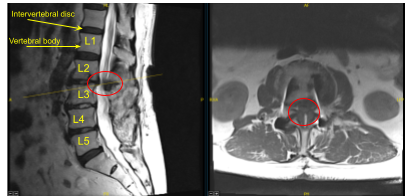

This patient had previously undergone an instrumented arthrodesis at an outside facility at L3-5. They presented with right anterior thigh and left posterior leg pain. Imaging displayed adjacent segment degeneration above and below her fusion mass which correlated well with her symptoms.